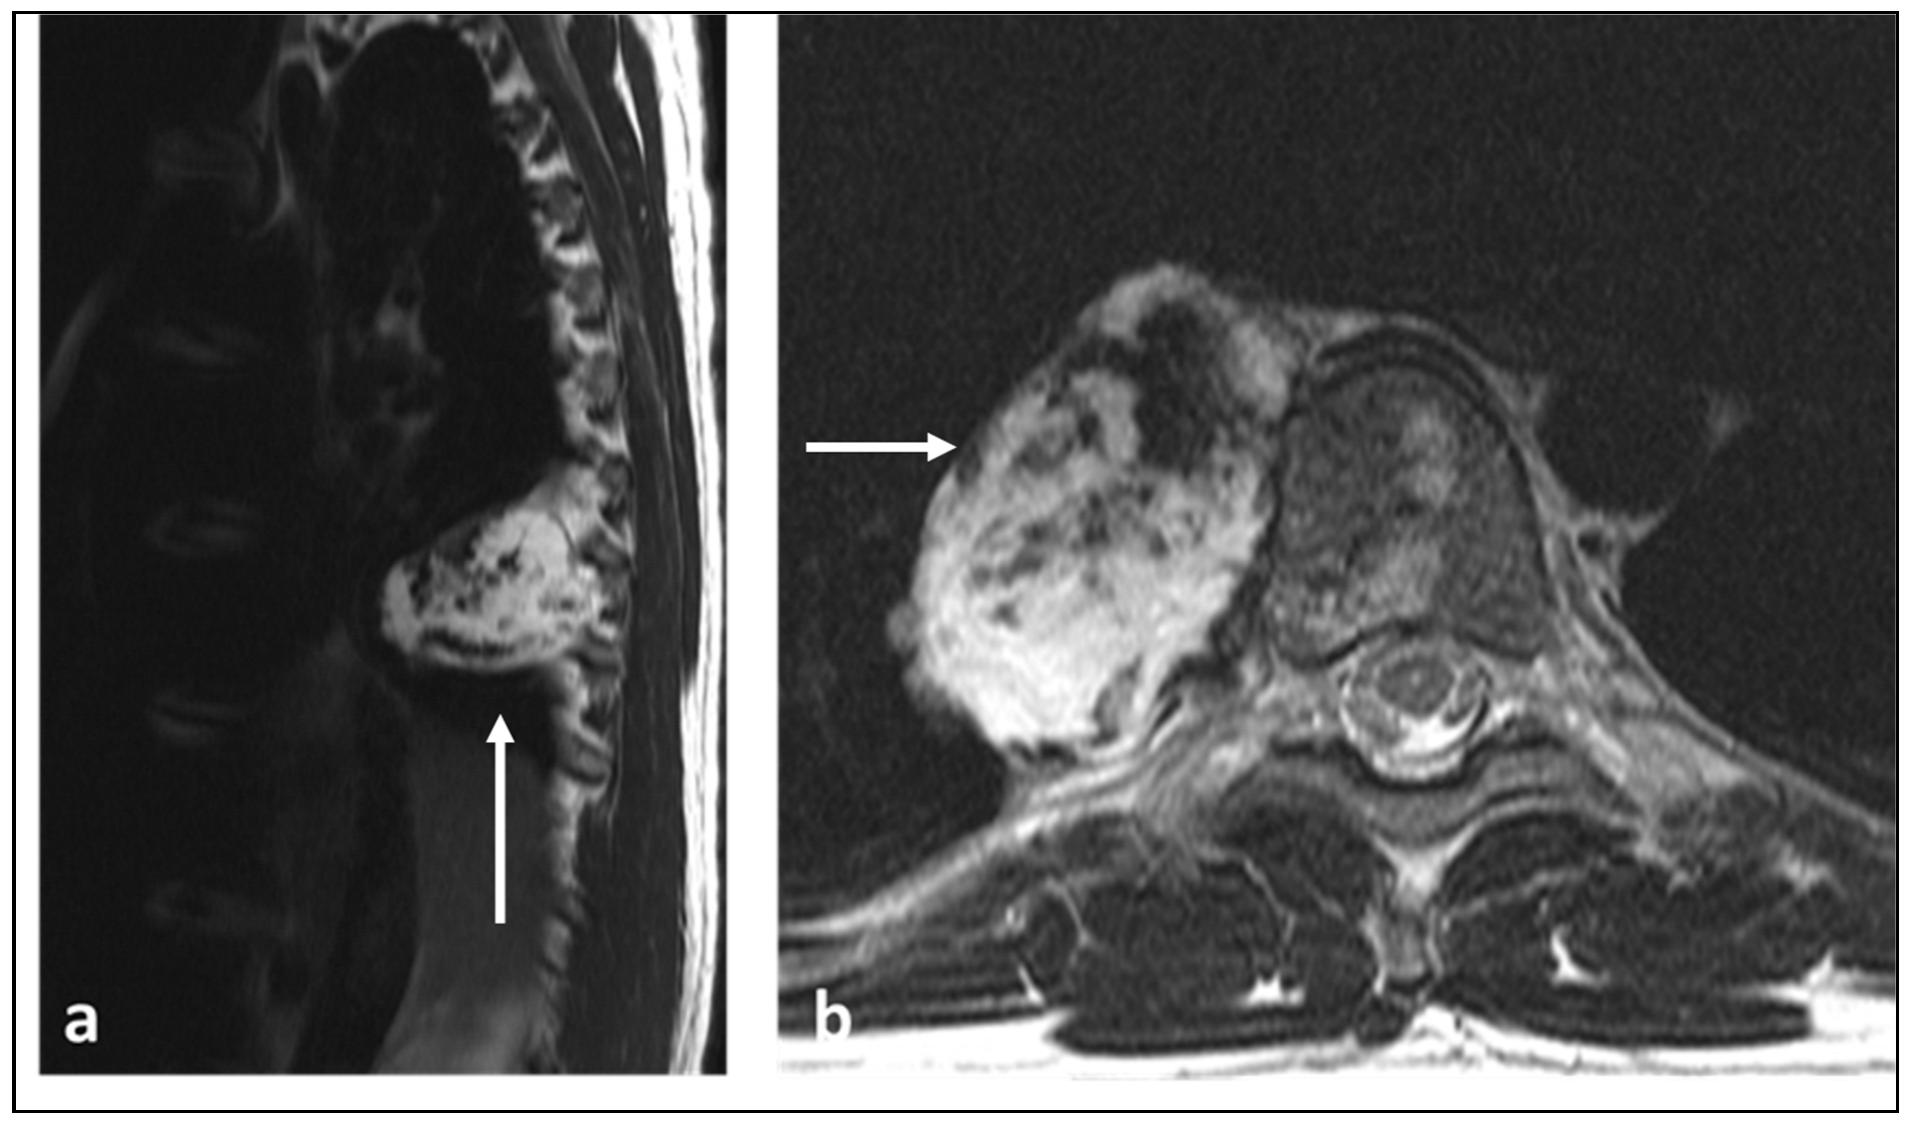

3.7. Angiosarcoma and Epithelioid Haemangioendothelioma (EHE)

| Angiosarcoma and Epithelioid Haemangioendothelioma | Lytic lesion. | High flow serpiginous vascular channels. |